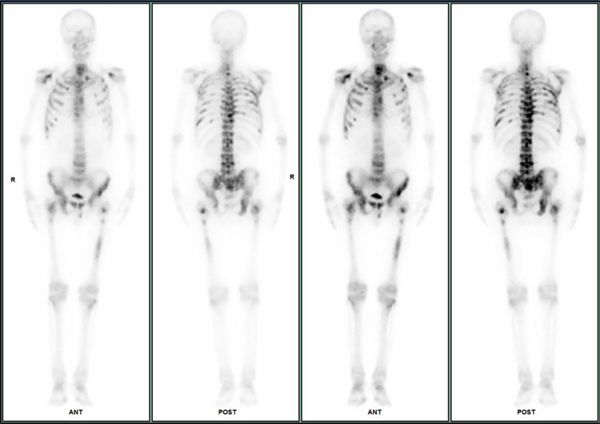

SPECT/CT全身骨显像 ——让骨骼病变无处遁形

SPECT全身骨扫描在早期诊断肿瘤骨转移方面具有得天独厚的优势,能及早发现病变,获得精准有效的治疗,期待更多患者从中获益。自设备投入使用以来,已有429人次接受了全身骨显像检查,检查阳性率高达95.8%(指所有异常骨骼显像)。这一高阳性率不仅凸显了SPECT/CT在检测各种骨骼病变方面的强大能力,也反映了在临床诊断和疗效评估中的不可或缺性。

病例1 患者女性,2024年2月无明显诱因下出现右侧胸背部持续性疼痛,至当地医院就诊,完善支气管镜检查并经我院病理会诊后诊断为“右肺鳞癌”,伴淋巴结、肝部和肝内胆管继发恶性肿瘤,为评估全身情况确定下一步治疗方案行全身骨显像,提示右肺鳞癌伴全身广泛骨转移。

病例2 患者男性,确诊前列腺癌6年余,规范行内分泌药物去势+抗雄治疗,期间定期复查,核医学科行全身骨显像,发现全身广泛骨转移。